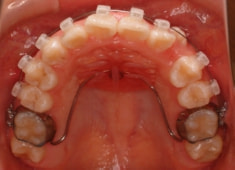

治療開始時